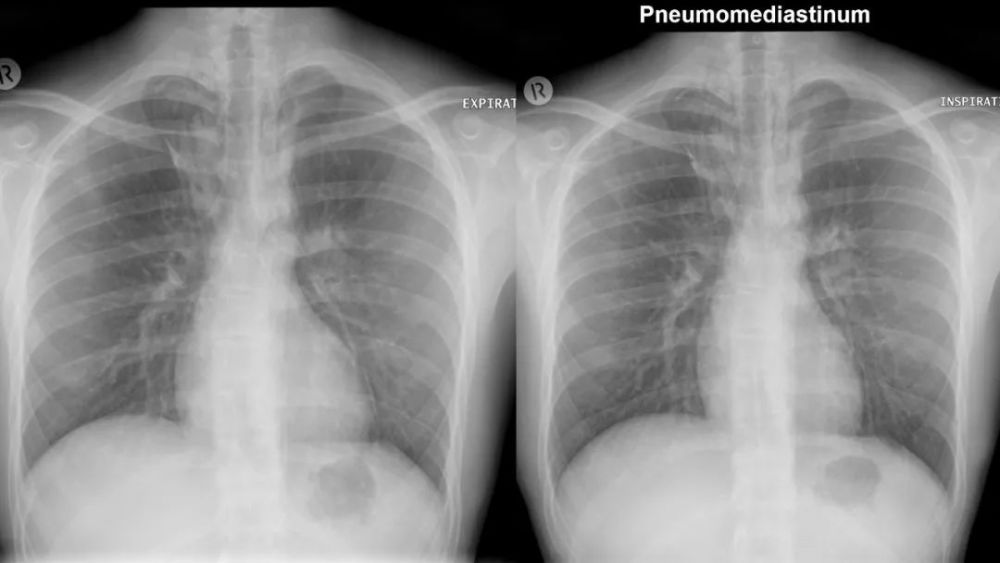

奇 裂

奇静脉分隔右肺上叶尖段

不是真正的附叶 , 因为没有自己的支气管 解剖标本的发生率为1% , M:F=2:1

X:细线状隆起(相对于纵膈) , 穿过右肺尖 , 前位上纵膈胸片可?气体

CT: 奇裂从SVC和气管后穿过